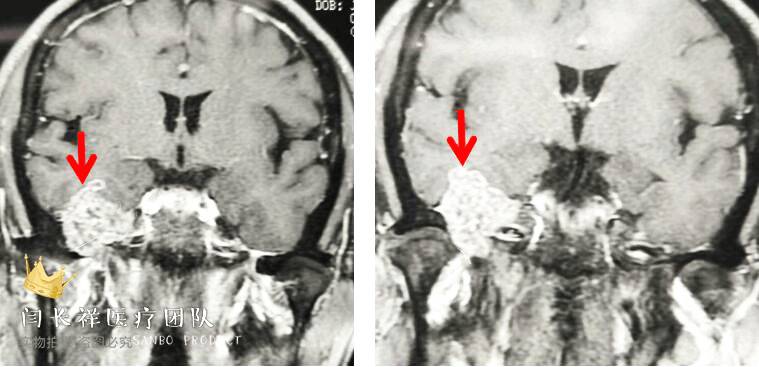

术前MRI轴位T1扫描示病灶呈等信号。

术前MRI轴位T2扫描示病灶侵及面神经膝段及中耳骨质。

术前MRI轴位T1增强示病灶显著不均匀强化。

术前MRI冠位T1增强示病灶主体位于硬膜外,侵蚀中颅窝底骨质并朝颞下窝、翼腭窝生长。